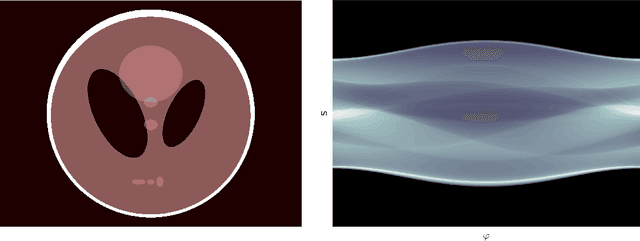

Abstract:Deep image prior was recently introduced as an effective prior for image reconstruction. It represents the image to be recovered as the output of a deep convolutional neural network, and learns the network's parameters such that the output fits the corrupted observation. Despite its impressive reconstructive properties, the approach is slow when compared to learned or traditional reconstruction techniques. Our work develops a two-stage learning paradigm to address the computational challenge: (i) we perform a supervised pretraining of the network on a synthetic dataset; (ii) we fine-tune the network's parameters to adapt to the target reconstruction. We showcase that pretraining considerably speeds up the subsequent reconstruction from real-measured micro computed tomography data of biological specimens. The code and additional experimental materials are available at https://educateddip.github.io/docs.educated_deep_image_prior/.